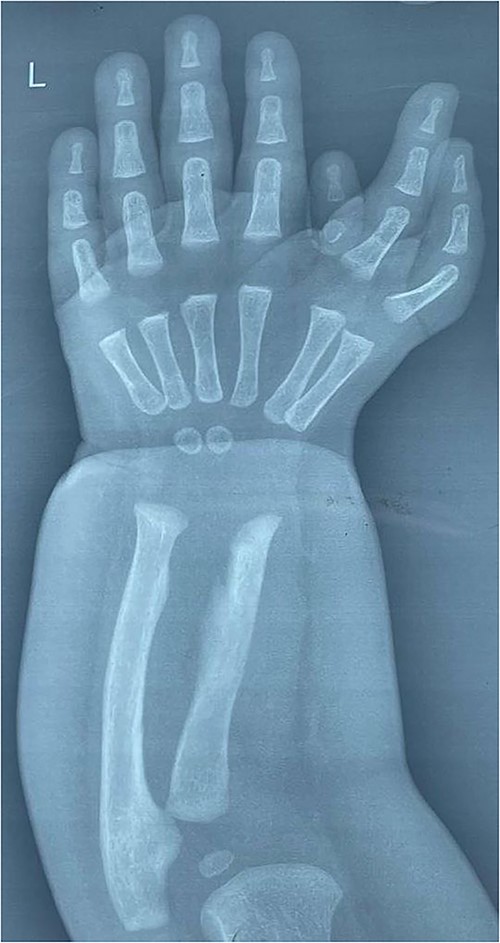

We find that our case was a non-classical ulnar dimelia as the patient has one radius and one ulna. The hand bears six triphalangeal digits with six corresponding metacarpals; there is also rudimentary finger that contains two bones only, which was the third finger. The wrist has two ossification centers correspondent to two capitates (Fig. 2).

Anteroposterior radiograph of the left wrist, showing one radius and one ulna, the wrist has two ossification centers, the hand bears six triphalangeal digits with six corresponding metacarpals arranged in two groups; there is also rudimentary finger that contains only two bones.